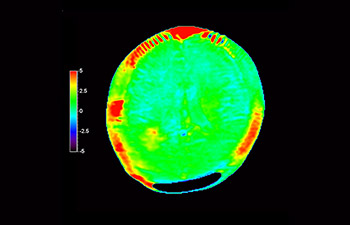

Glioblastoma image

Brain with glioblastoma

with 3D APT